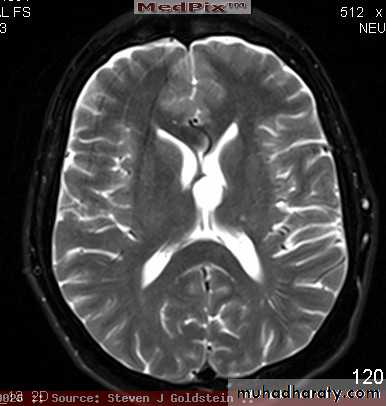

COLLOID CYST OF 3rd VENTRICLE

C. CYST OF 3rd VENTRICLE T2 MRI